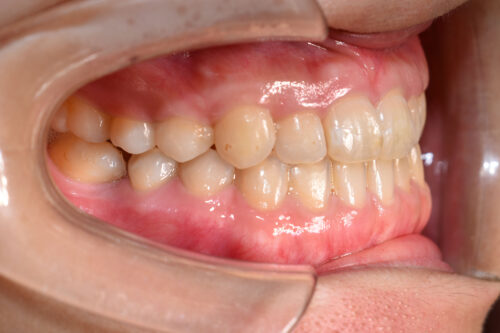

初診時年齢 28歳 女性

歯のでこぼこ(叢生)

下顎右側第一大臼歯欠損(歯をぬいた)

を主訴に

池袋よりひとつ隣駅の東京都豊島区大塚駅すぐの大塚たまみ矯正歯科へ

いらっしゃいました。

歯のがたつき (叢生)

と

受け口が認められました。

本症例も

下顎右側第一大臼歯欠損

上下とも歯が唇側に傾斜し

下の歯が上の歯よりも外にでている 受け口の状態でした。

ワイヤー8か月後です。